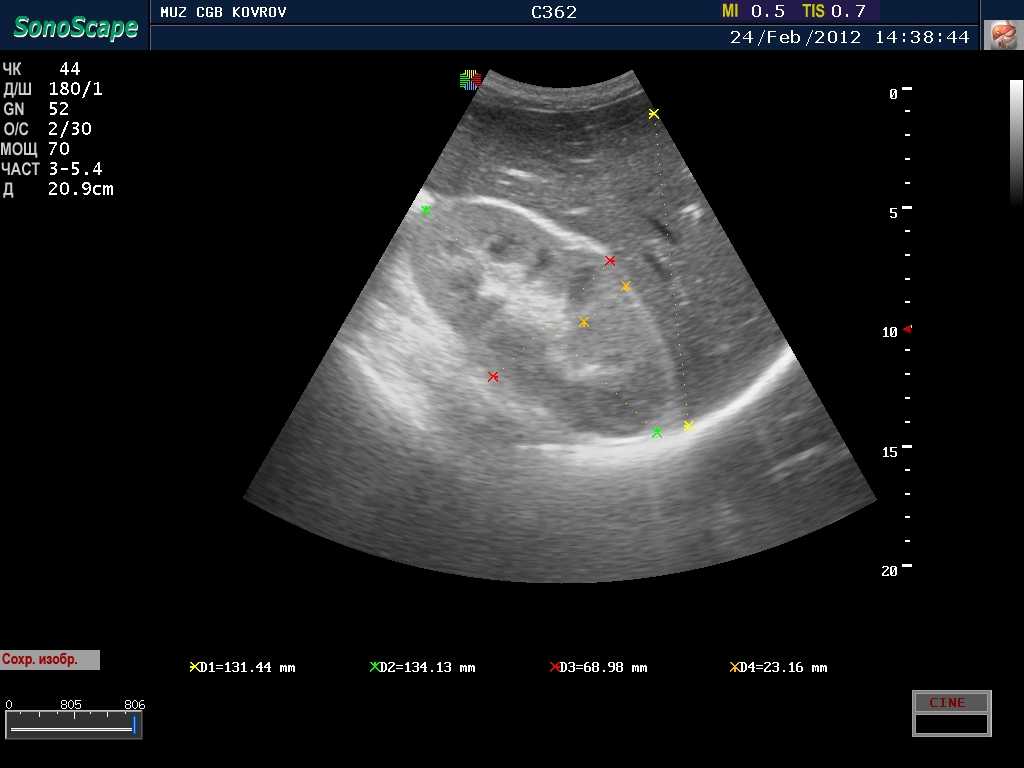

Уплотнения почечных синусов представляет собой изменения в структуре паренхимы органа, возникающие под воздействием воспалительного процесса. При таких нарушениях наблюдаются проблемы с кровоснабжением и микроциркуляцией в соединительной ткани. Эти изменения возникают как естественная реакция организма на течение воспалительного процесса. При обследовании на УЗИ уплотнения почечных синусов выявляются виде участков повышенной эхогенности.

Наиболее оптимальным методом исследования почек считается УЗИ. Ультразвуковое воздействие позволяет быстро обнаружить места, где образовались характерные уплотнения. Посредством УЗИ легко выявляются кисты в почечных синусах. Такие новообразования на экране монитора видны в виде округлых объектов с четкими контурами.